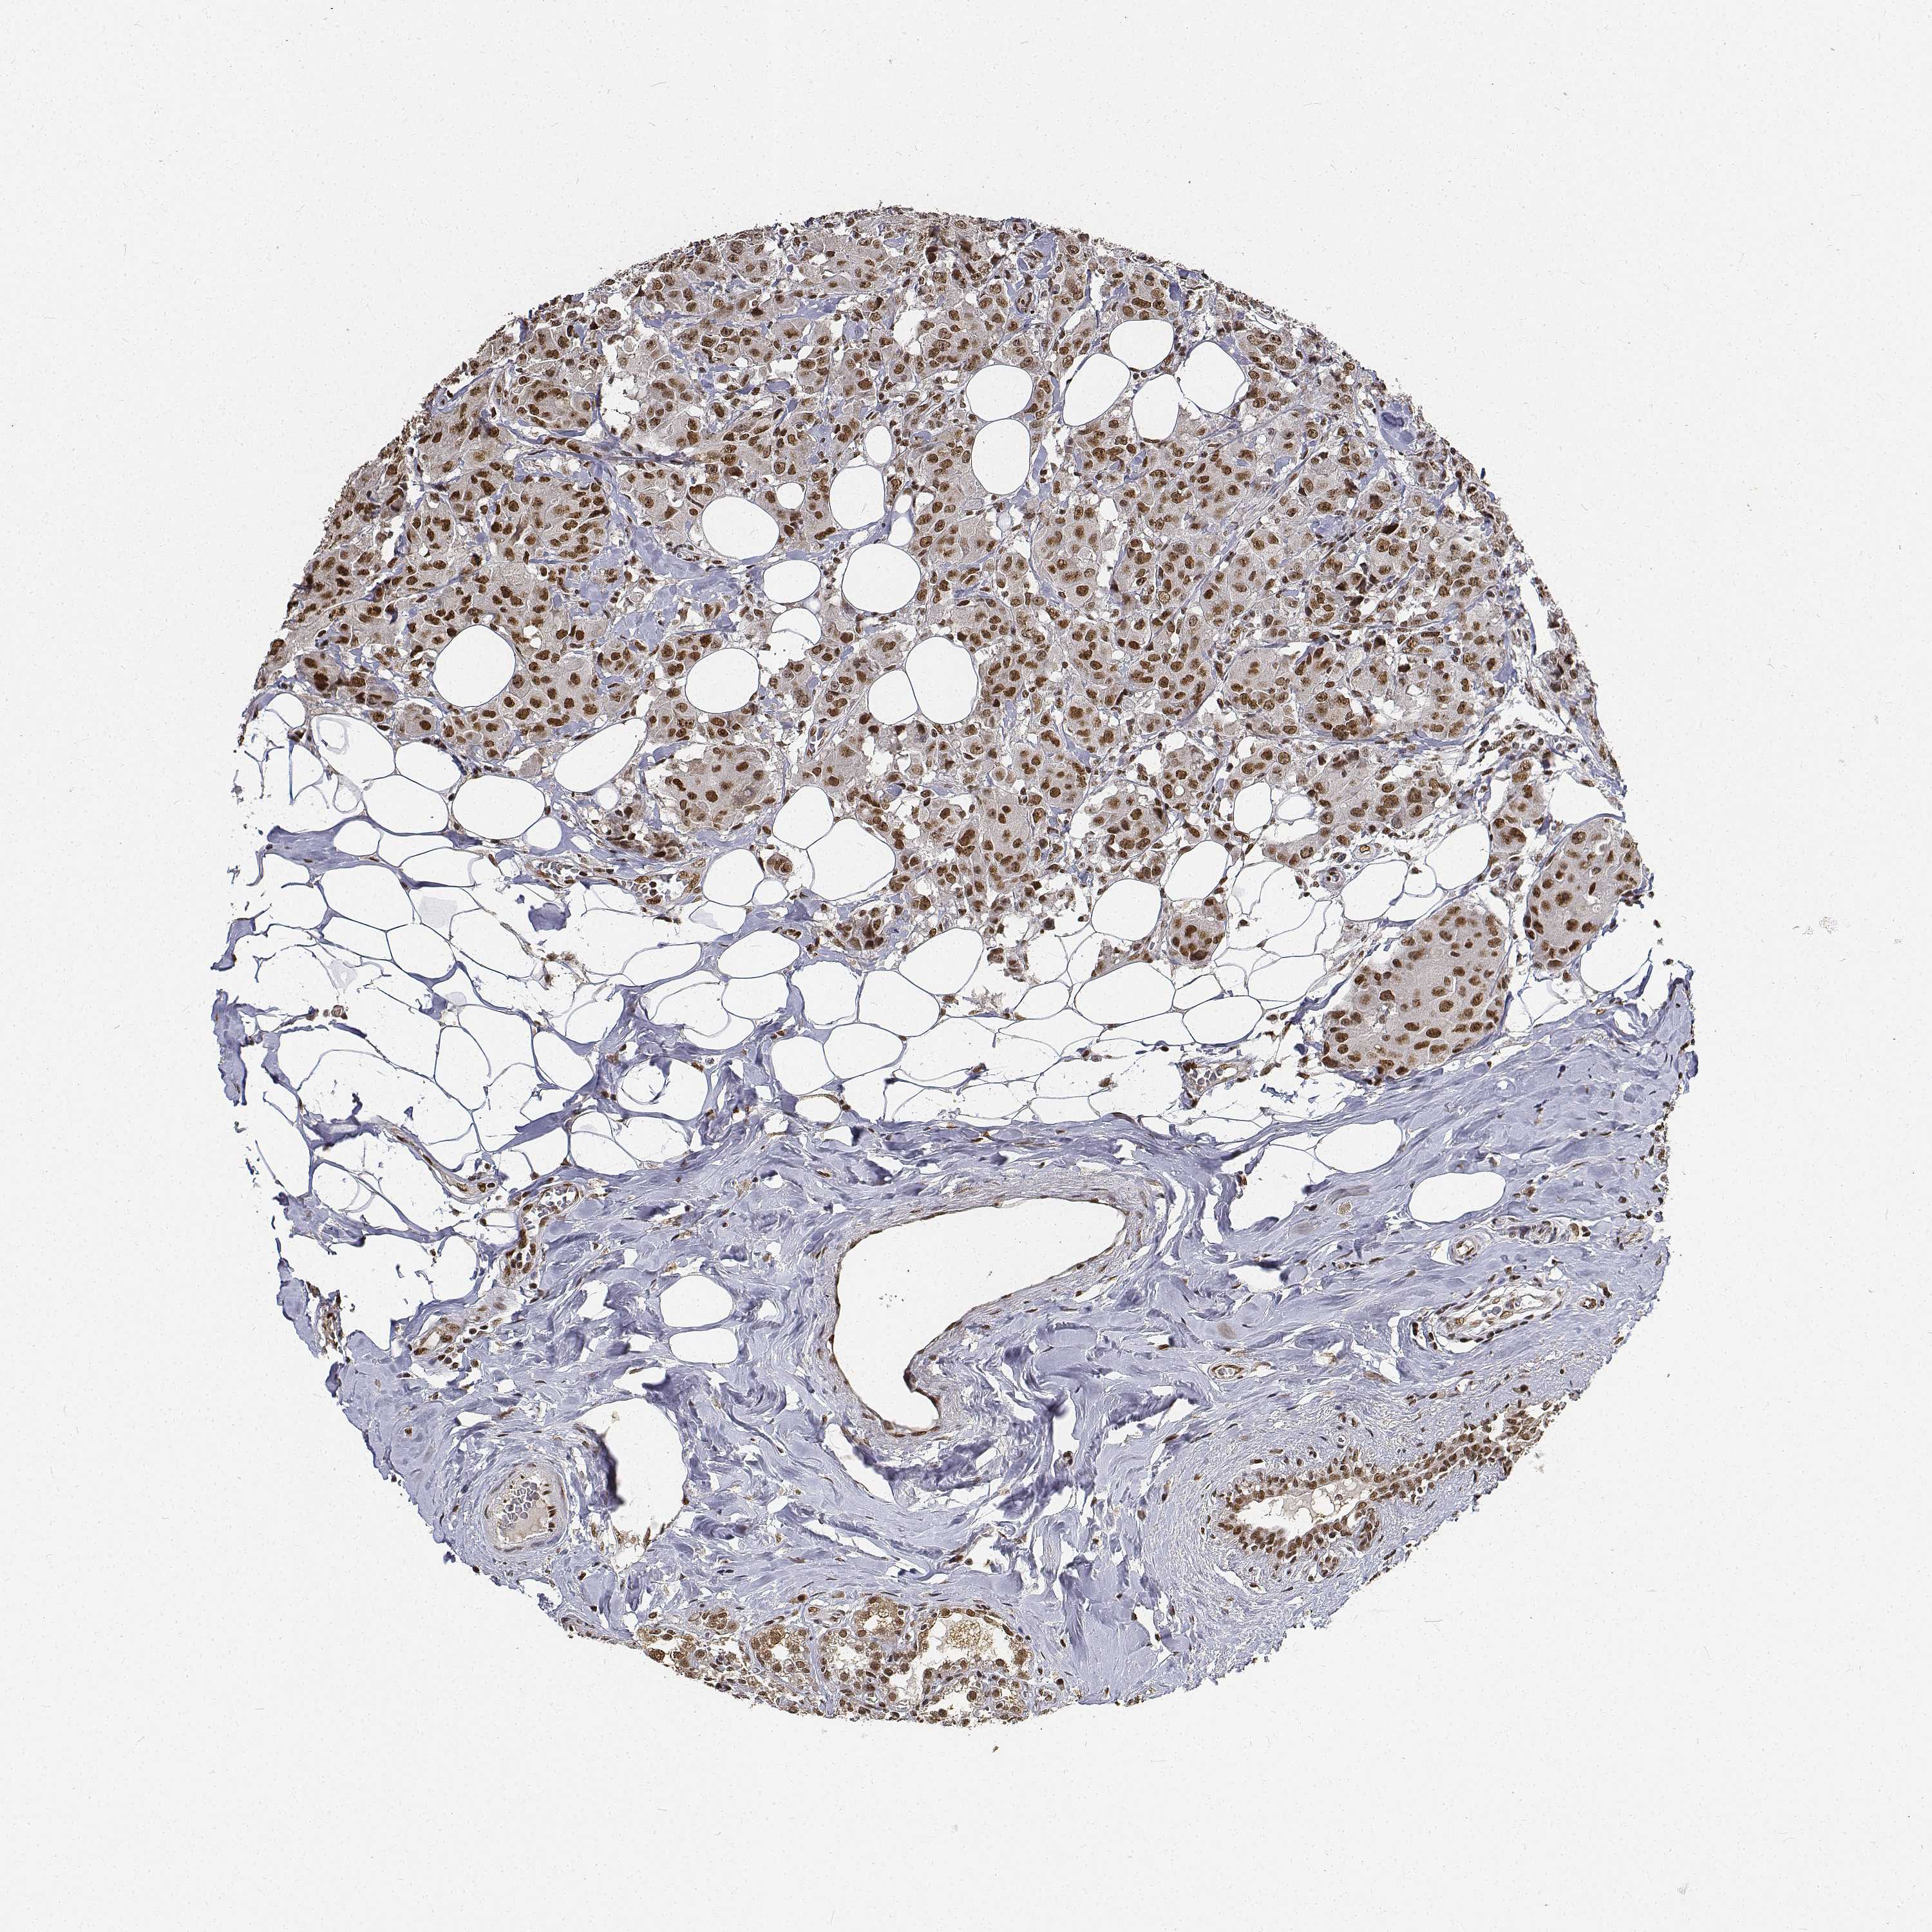

CANCER BREAST CANCER Show tissue menu

BRCA TCGA BRCA VALIDATION PROTEIN EXPRESSION

ANTIBODIES

AND

VALIDATION